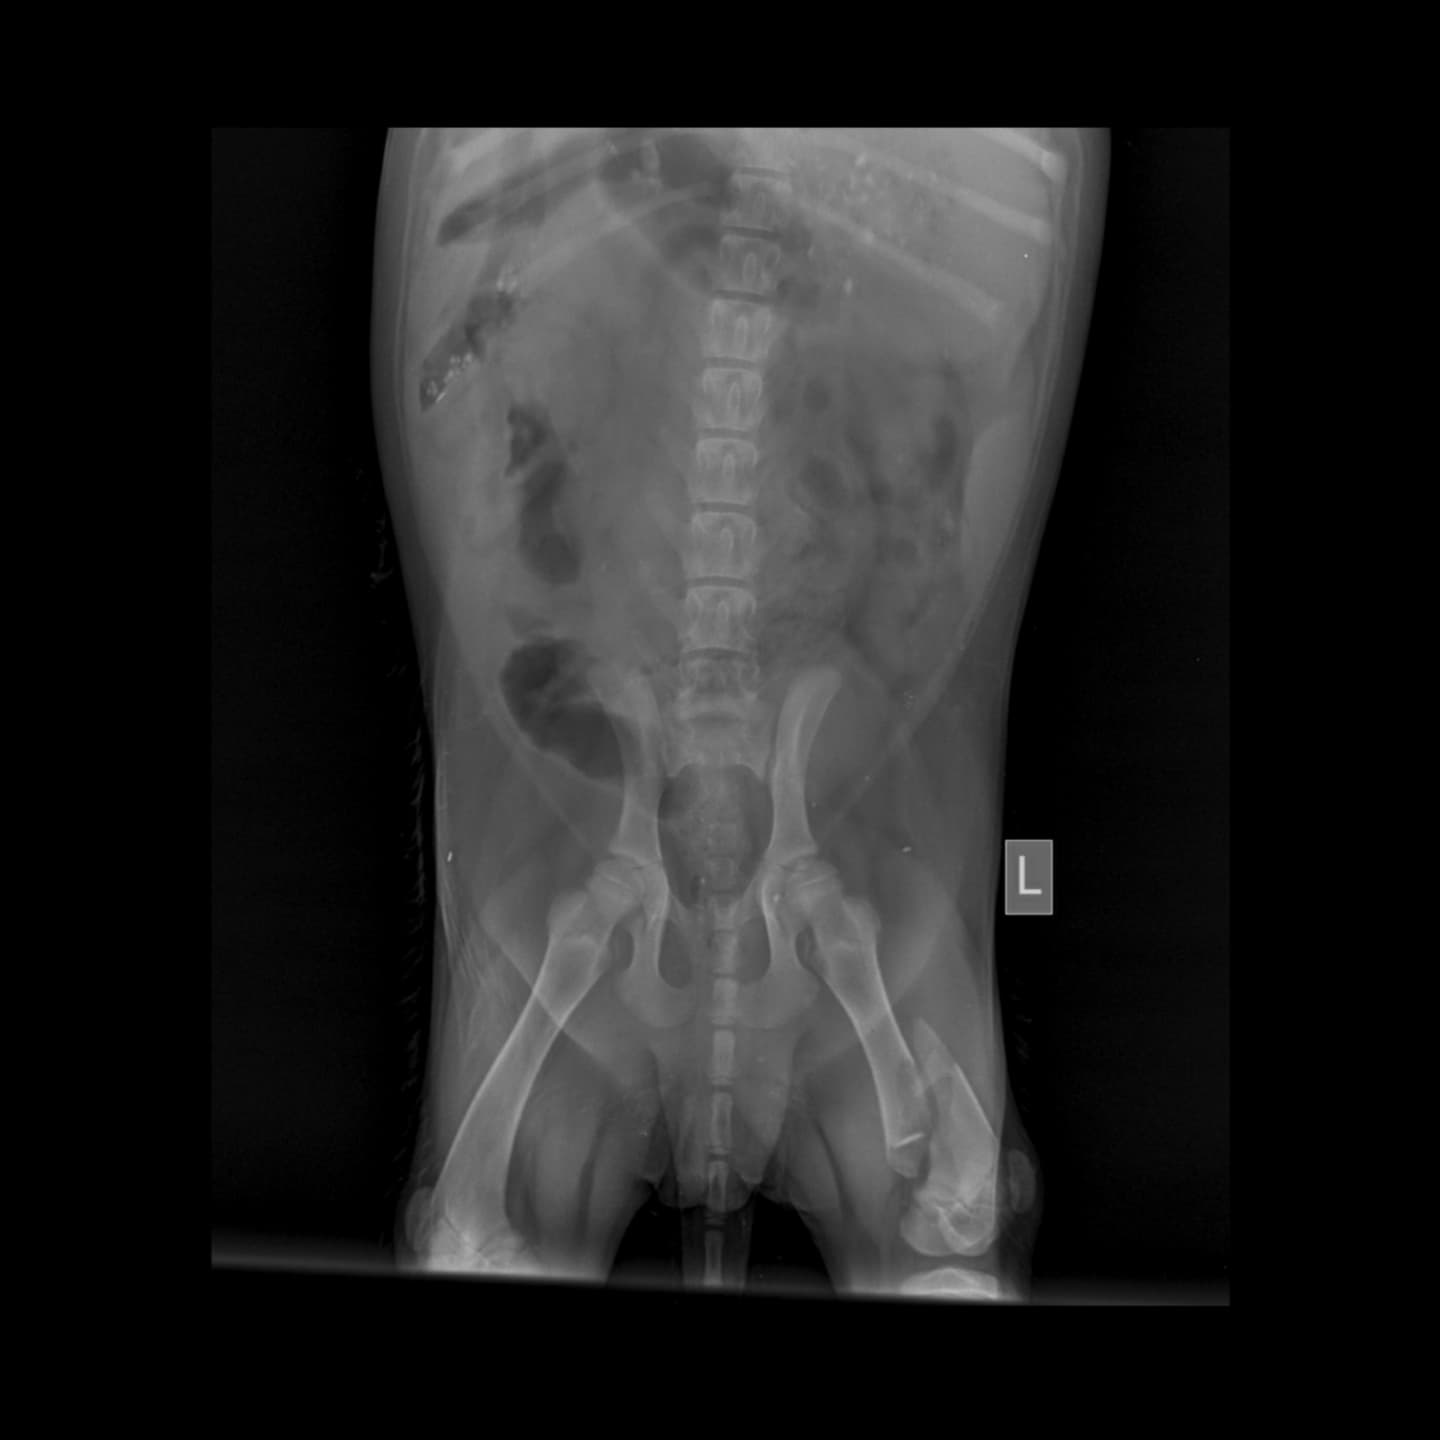

This little girl, MAPLE, all of 4-5 months was in a hit and run this evening. Second case within an hour of each other. The other one was killed on the spot. This one has multiple fractures on her leg. It’s a long road to recovery. We don’t know how and what is going to happen . Initial check up has been done and we have been informed that she will need surgery. Surgery is going to cost 25-30k and then shelter/foster care .

The last pic is today’s initial bill.